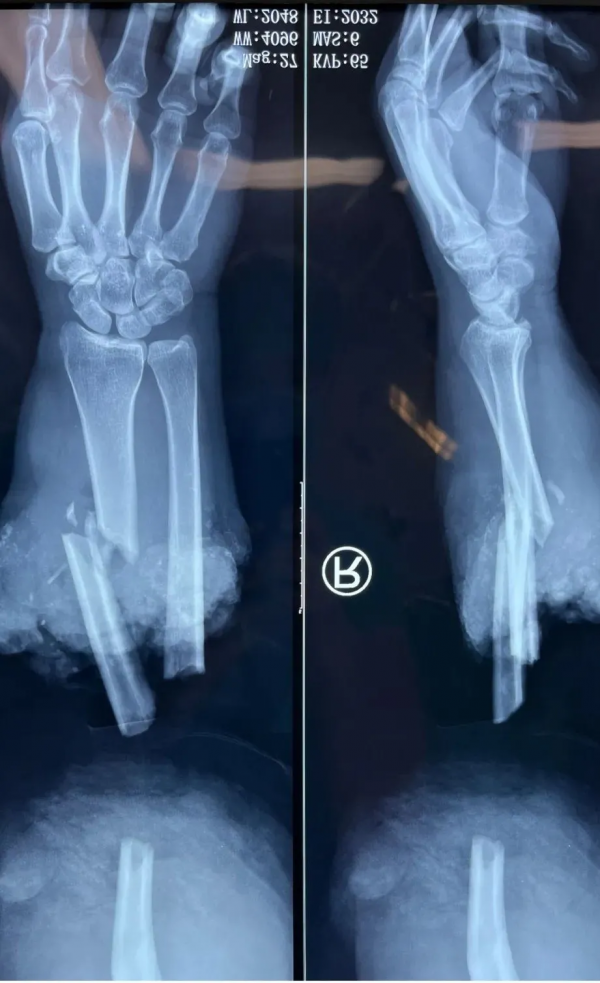

患肢離斷平面位於前臂中段,離斷肢體外觀完整,但創面汙染、面板挫傷嚴重,斷端肌肉肌腱、神經、血管都嚴重撕脫,初步判斷具備再植條件。二線武競衡醫師及三線童德迪主任醫師組成急診治療小組,手外科肢體顯微修復重建中心慄鵬程主任醫師協同制訂手術方案。

患者接進手術室後,手術團隊迅速完成斷肢近端的清創,吻合尺橈動脈及伴行靜脈、淺靜脈,尺神經自近端抽脫,傷口內無法探及,將正中神經近端與正中神經和尺神經遠端縫合,以期恢復患者手部保護性感覺。